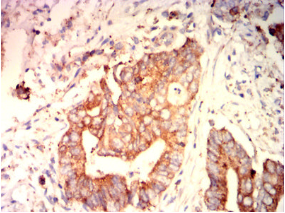

IHC    1/200-1/1000